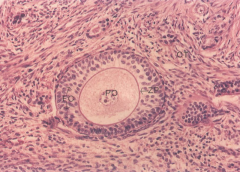

子宫腺肌瘤和子宫肌瘤的区别子宫肌瘤:是最常见的子宫良性肿瘤,主要是子宫肌层本身的平滑肌增生形成的。 子……